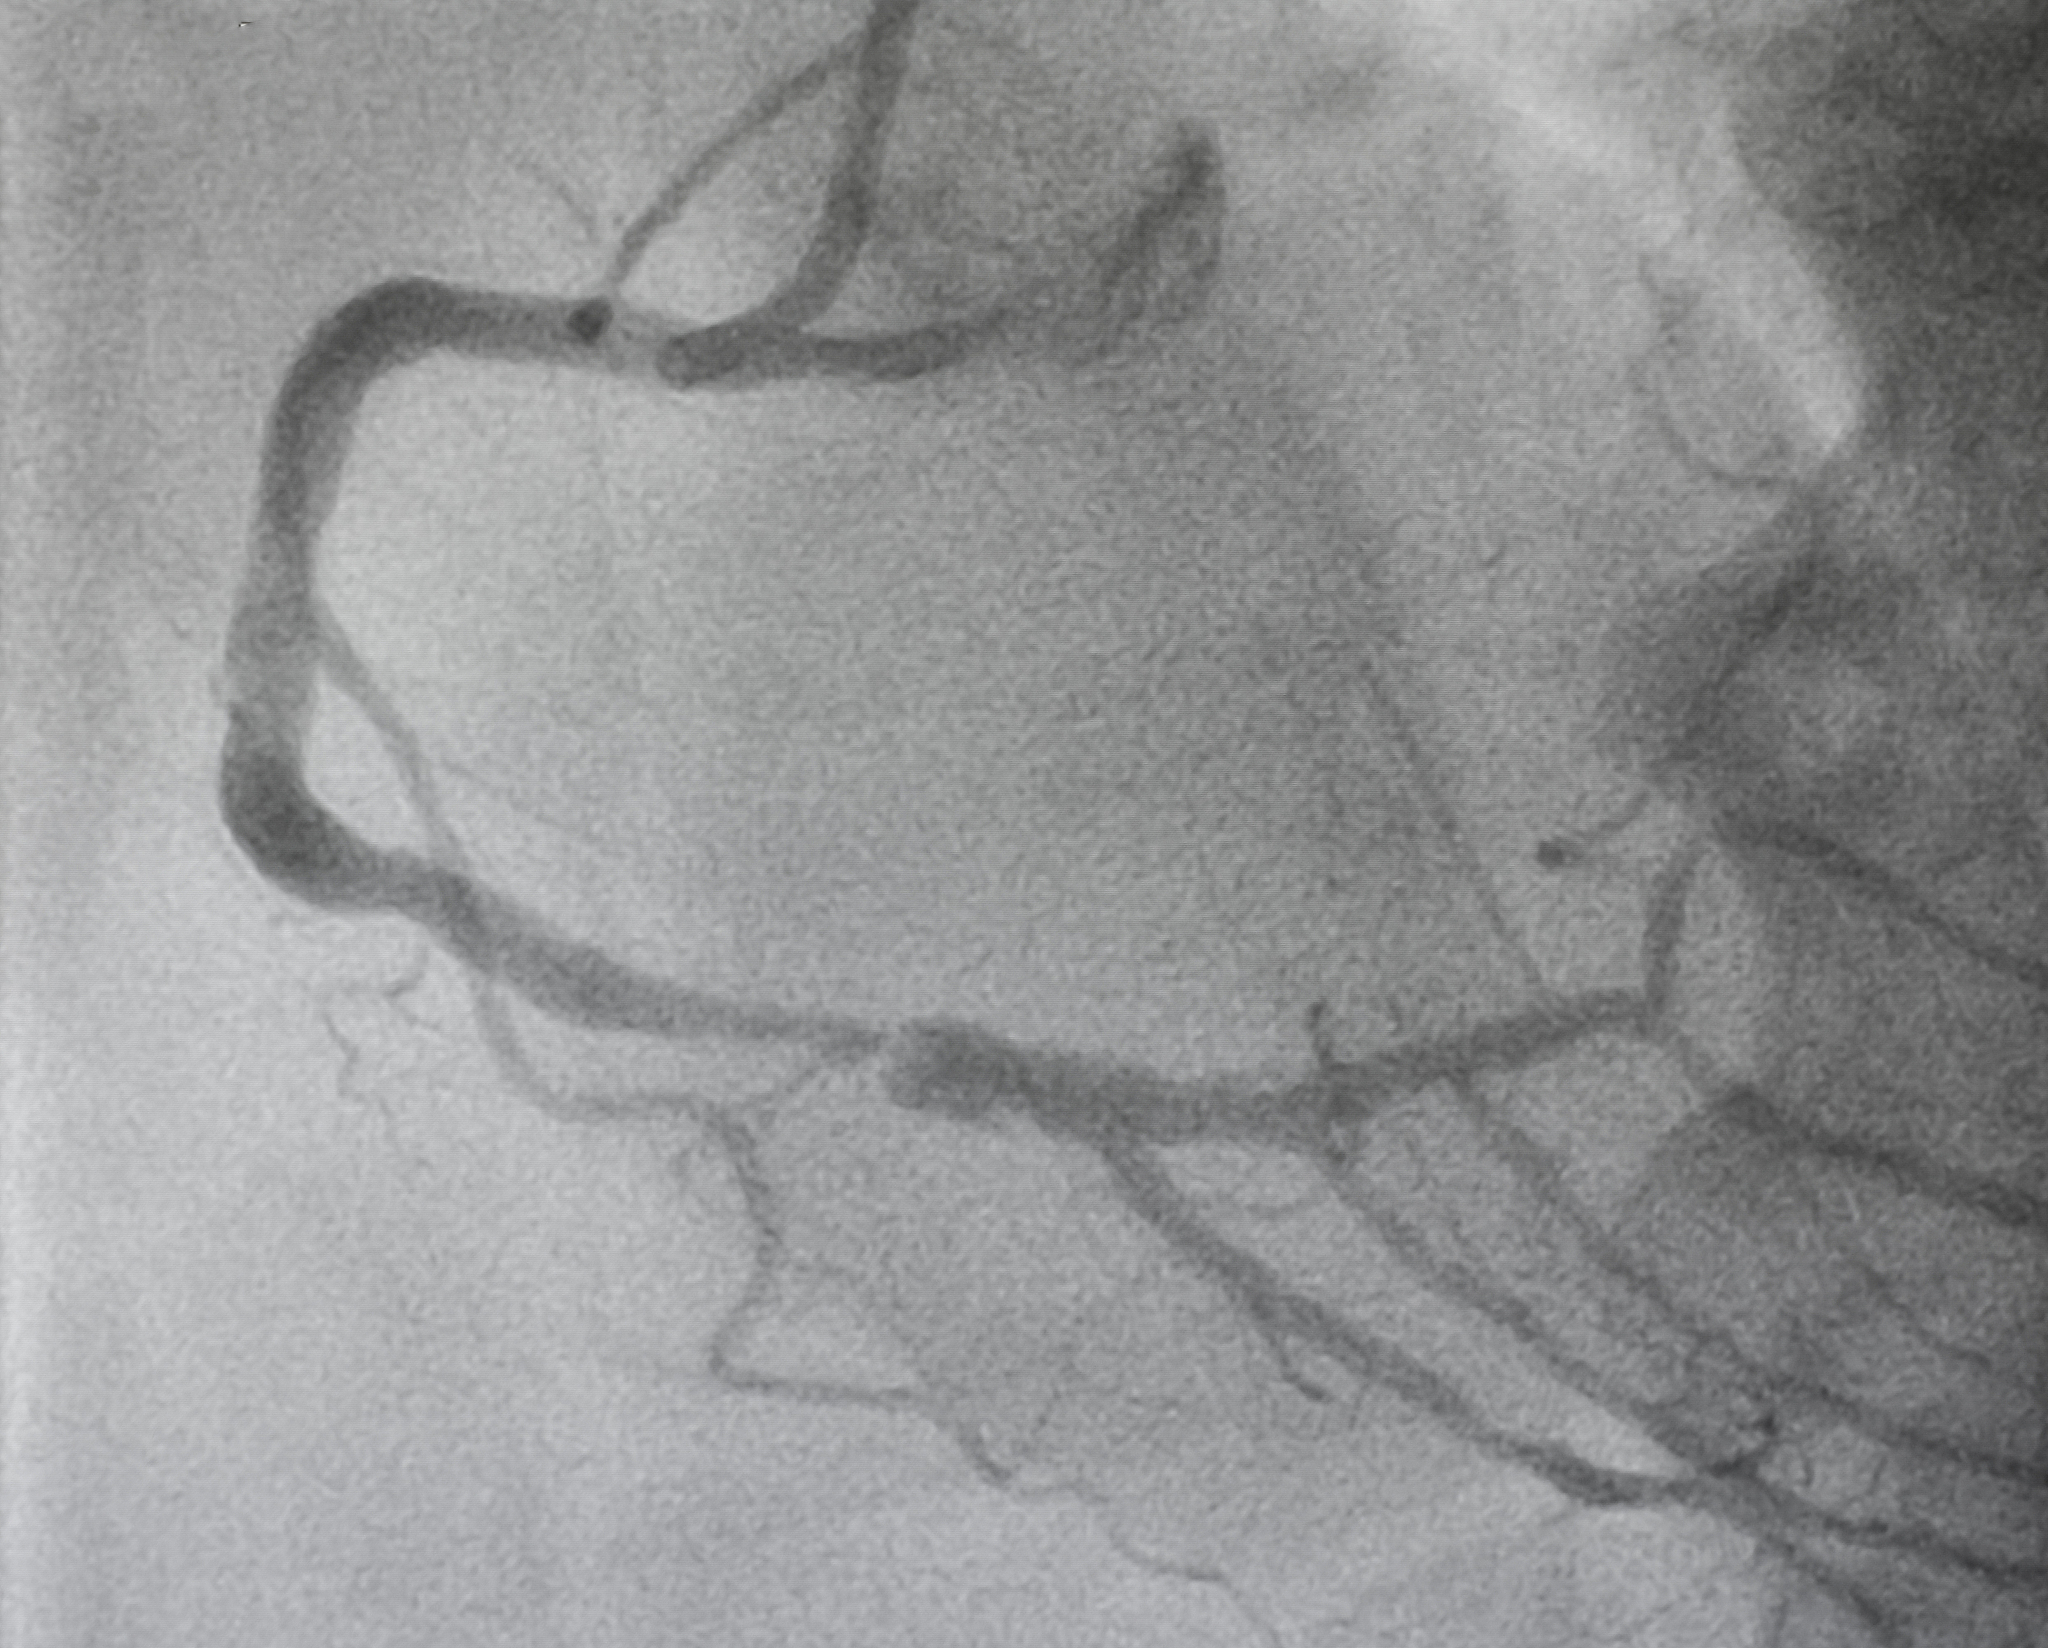

颈动脉斑块溃疡是指由于斑块破裂后脂质坏死物质被释放入血,形成的至少1×1mm的凹陷,颈动脉管腔内血液和造影剂可与之相通。